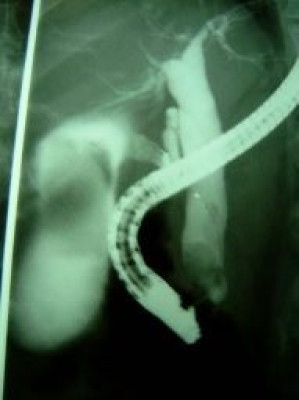

Colelitiasis y coledocolitiasis ERCP

Envíado por Dr. Carlos Miguel Zavaleta Consuegra